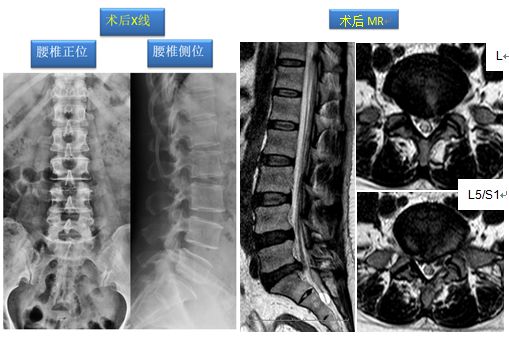

该手术在梁徳主任指导下由江晓兵副教授按照标准化流程顺利完成,将致压物进行了彻底摘除,神经压迫顺利解除,并进行植骨及钉棒系统内固定。术后复查如下:

手术后患者原有症状完全消除,但1个多月后,该患者来到门诊后询问我科江晓兵副教授:“为什么我做了手术后刀口周围会痛呢?”,在我科筋骨并重查体评估原则指导下,我们进行了仔细的触诊评估,发现手术切口周围有显著的筋膜肌肉粘连,这样的现象在部分患者中会发生,与术后伤口周围炎症反应有关,周围肌肉筋膜粘连会引起患者疼痛不适,有些患者术后长期伤口周围疼痛就是这样的机制。发现了病因解决起来就很容易,使用棍点手法治疗2次后,患者伤口周围变硬、粘连的筋膜肌肉恢复至正常状态,疼痛也完全消除了。